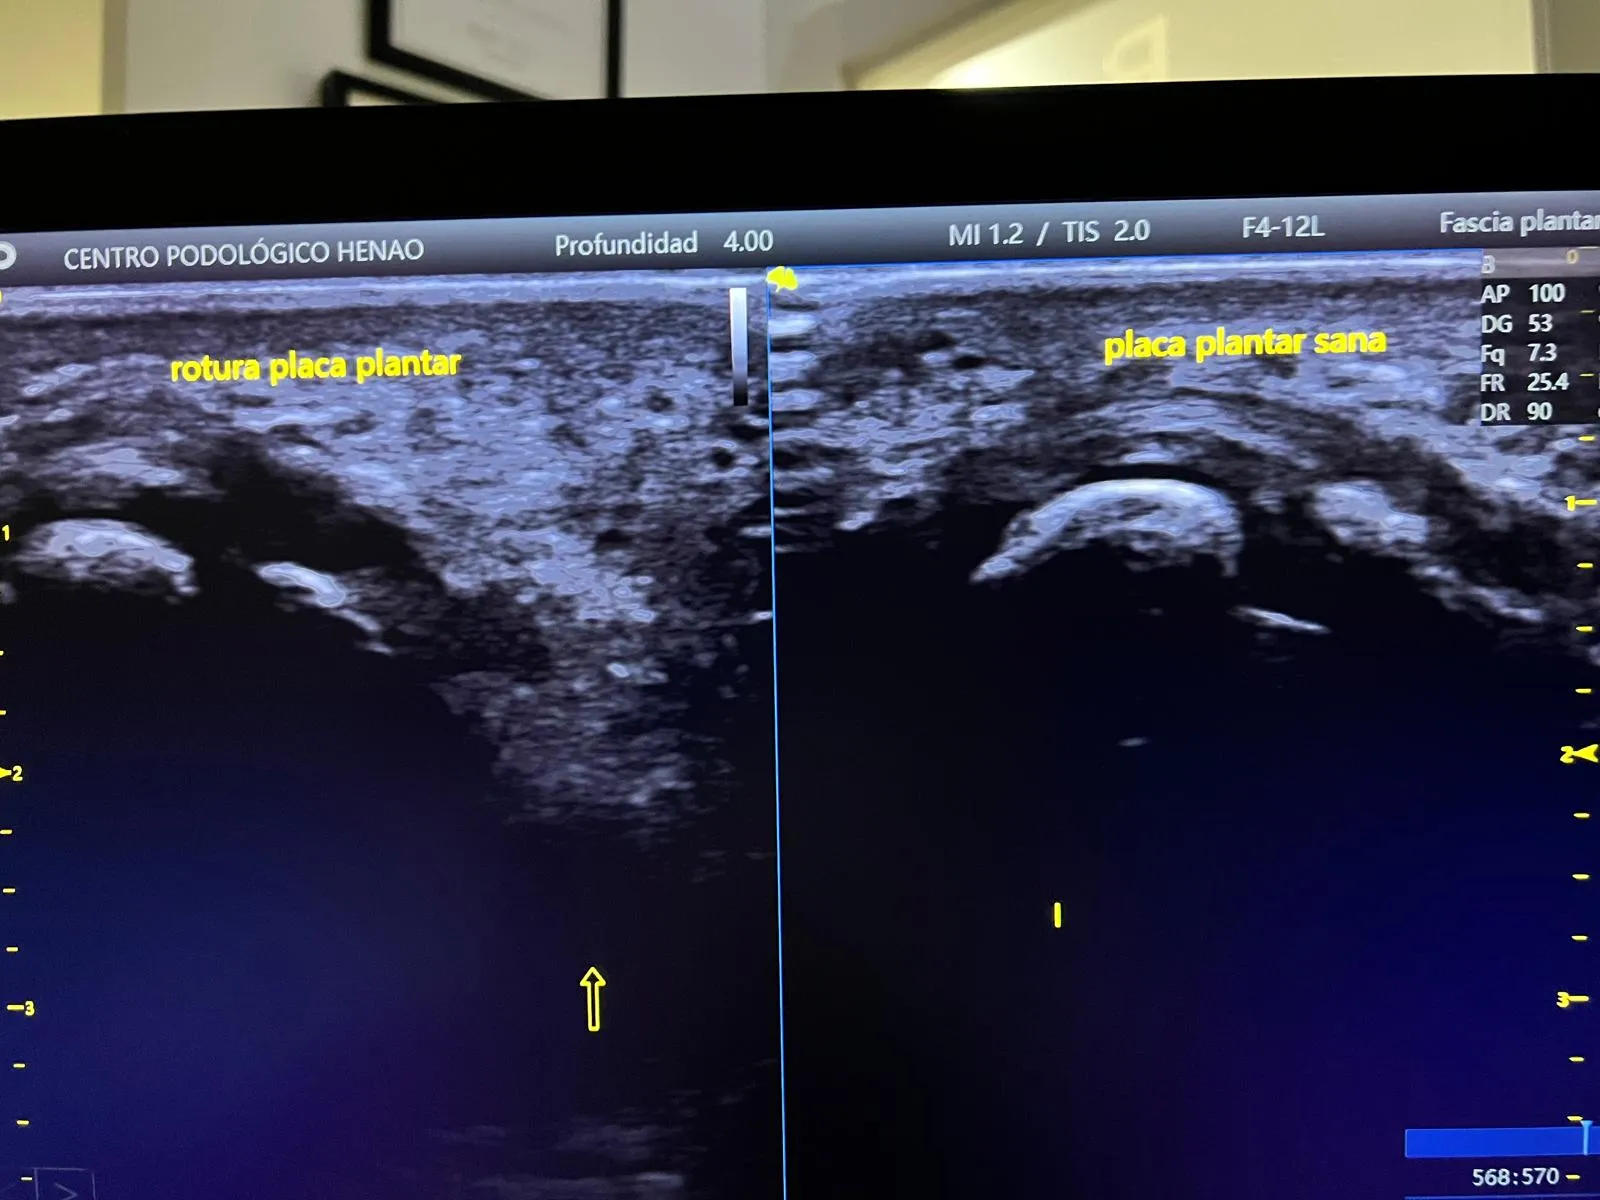

La Imagen Ecográfica: Placa Plantar Sana vs. Placa Plantar Rota

Una de las claves de este caso fue poder mostrarle al paciente, en tiempo real, la diferencia entre su placa plantar afectada y la del pie sano. La ecografía musculoesquelética permite esta comparación de forma inmediata, sin radiación y con una resolución suficiente para identificar roturas, adelgazamientos y cambios en la ecoestructura del tejido.

En la imagen superior puedes ver la comparativa ecográfica: a la izquierda, la placa plantar afectada del tercer metatarsiano, donde la continuidad del tejido aparece interrumpida con signos de edema perilesional; a la derecha, la placa plantar íntegra del pie sano, con su estructura fibrilar característica bien definida. Esta imagen fue determinante para confirmar el diagnóstico, orientar el tratamiento y explicarle al paciente de forma visual qué le estaba ocurriendo exactamente.